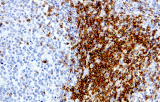

- Assegnazione del lignaggio & principali diagnosi differenziali: Fenotipizzazione cellule B vs cellule T (es. CD20 vs CD3), supportata da fattori di trascrizione nucleari delle cellule B come PAX5 quando i marcatori pan-B sono deboli/assenti.

- LLC/LLS: co-espressione caratteristica di CD5 e CD23 nelle cellule B CD20+ (l'interpretazione richiede consapevolezza del pattern perché sono presenti cellule T reattive).